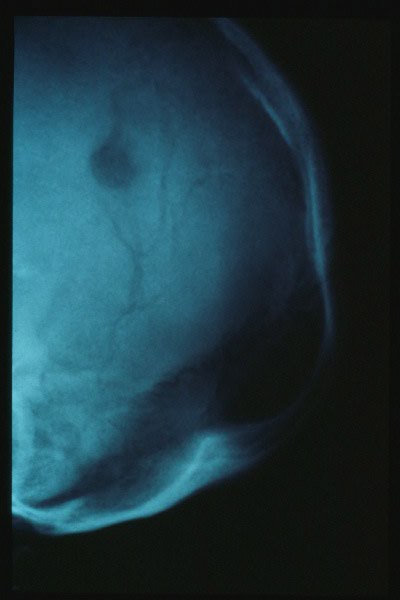

Osteoporosis circunscrita en Enfermedad de Paget.